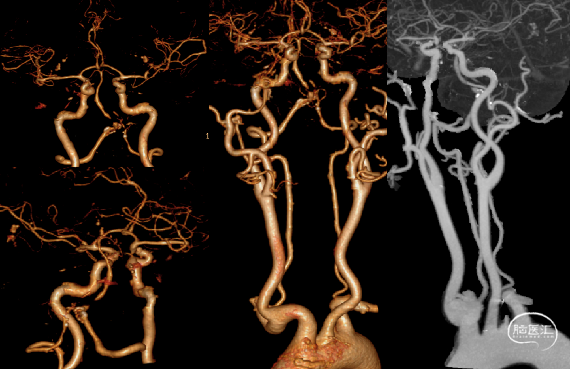

CTA:椎基底动脉连接处重度狭窄;多发脑动脉狭窄。

右侧桡动脉穿刺造影:右侧椎动脉优势;左侧椎动脉发自弓上,纤细迂曲;双侧后交通动脉欠发达。

超选右侧椎动脉造影:右侧椎-基底动脉连接处次全闭塞,前向血流 mTICI 2b级。

举例图片,非上述病例患者